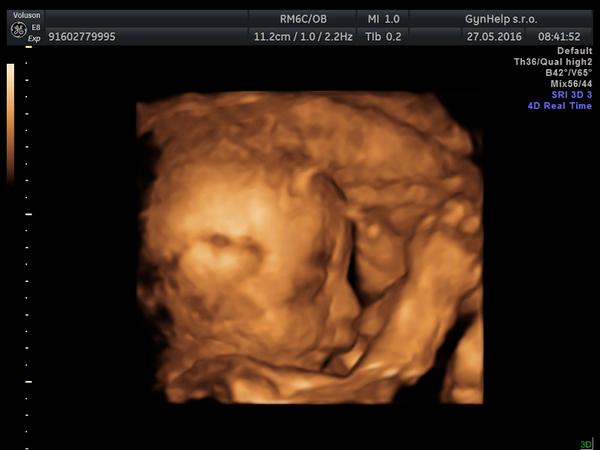

Rozštěp rtu podle 3D ultrazvuku?

ahoj holky dnes jsem byla na 3D ultrazvuku a dost som sa vydesila s pohladu na rtiky malyho,mam pocit ze neco neni v poradku.. doktorka byla neprijemna nechtela mi na nic odpovedet a tak jsem si jen vzada foto a sla :,( muzete mi prosim rict jestli je to podle fotek normalní nebo se jedna o nejaku vrozenou vadu? prosim bez blbych komentov opravdu jsem z toho spatna! dekuji moc

Podle fotek z 3D utz nelze soudit že jde o rozštěp rtu. Ale pro tvůj klid až půjdeš na kontrolu vezmi sebou foto a zeptej se na to gynekologa. Nevím jestli ta lékařka je i tvoje ošetřující gynekoložka nebo zda jsi u ní byla jen na 3D utz.

Nic to nebude,taky jsem na 3D furt viděla nějaké čárky na rtu a děsila se. Ale jsme laici a i když technologie jsou vyspělé tak to není jako obraz v zrcadle, může to být stín, různě mázlé, záleží na úhlu záběru. Buď v klidu, doktor by ti to určitě řekl.

Řekni svému gynekologovi, ať se na to provtvůj klid podívá ještě na normálním utz, tam by to mělo být vidět. Máme rozštěp v rodině, tak mě taky hlídal a z normálního utz vyloučil. Podle fotek bych řekla, že tam rozštěp není, ony ty 3D utz jsou takové celé rozvlněné, krabaté.

Tak můj manžel (MUDr) ti vzkazuje 😀 , že 3D UZ nejsou absolutně k diagnostice, že tohle je evidentně chyba toho ultrazvuku a rozhodně to neznačí rozštěp rtu. Prý jsou 3D ultrazvuky pro maminy, aby se chlubily 😀 (nedopřál mi ho.. 😀)

@veruncca ahojky dopadlo to dobre malej jeb moc kroutil s pusinkou a tak se to spatne vyobrazilo na ultrazvuku. Držím palce at je vše v poradku ❤️